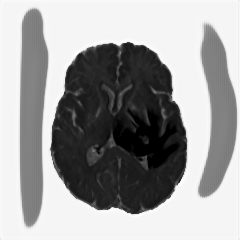

We obtain a subject-wise mean Dice score of 32.94% without any post-processing. By using a simple post-processing with erosion and dilation with filters, this number improves to 48.20% mean Dice score. In comparison, a similar study conducted by [3] consisting of a multitude of algorithms including AnoVAEGAN [4] and f-AnoGANS, obtained a best mean score of 27.8% Dice after post-processing by f-AnoGANS. Before post-processing the best method was Constrained AutoEncoder [8] with a score of 9.7% Dice. An exhaustive list is presented in Table 1. Figure 4 shows sample images of our results.

We obtain a subject-wise mean Dice score of 63.67% for the brain tumor segmentation. Utilizing a simple post-processing scheme of erosion and dilation with filter, we improve our mean Dice score to 68.01%. Figure 4 shows samples generated by our ASC-Net and Table 2 shows our before and after post-processing results. We attempted to apply f-AnoGANs [34] by following their online instructions and failed to generate good reconstructions as shown in Figure 5. The failure of AnoGANs in the reconstruction brings to light the issue with the regeneration based methods and the complexity and stability of GAN-based image reconstruction.

We obtain a slice-wise mean Dice score of 32.24% for this liver lesion segmentation, which improves to 50.23% by using a simple post processing scheme of erosion and dilation with filter. Sampled results are shown in Fig. 4. Compared with [42], which obtains a mean Dice score of 40.78% and a standard deviation of 0.43%, we improve the mean Dice score by almost 10%, but has a much larger standard deviation. Unlike [42], where the network is pre-trained on a artificial tumor dataset, and hence the pipeline customized for tumor segmentation, our method do not need such information beforehand. We notice that our standard deviation for BraTS dataset is similar to [27]. This is because novelty/anomaly detection algorithms without a pre-defined task would suffer from the co-morbidities issues discussed in Section 5.